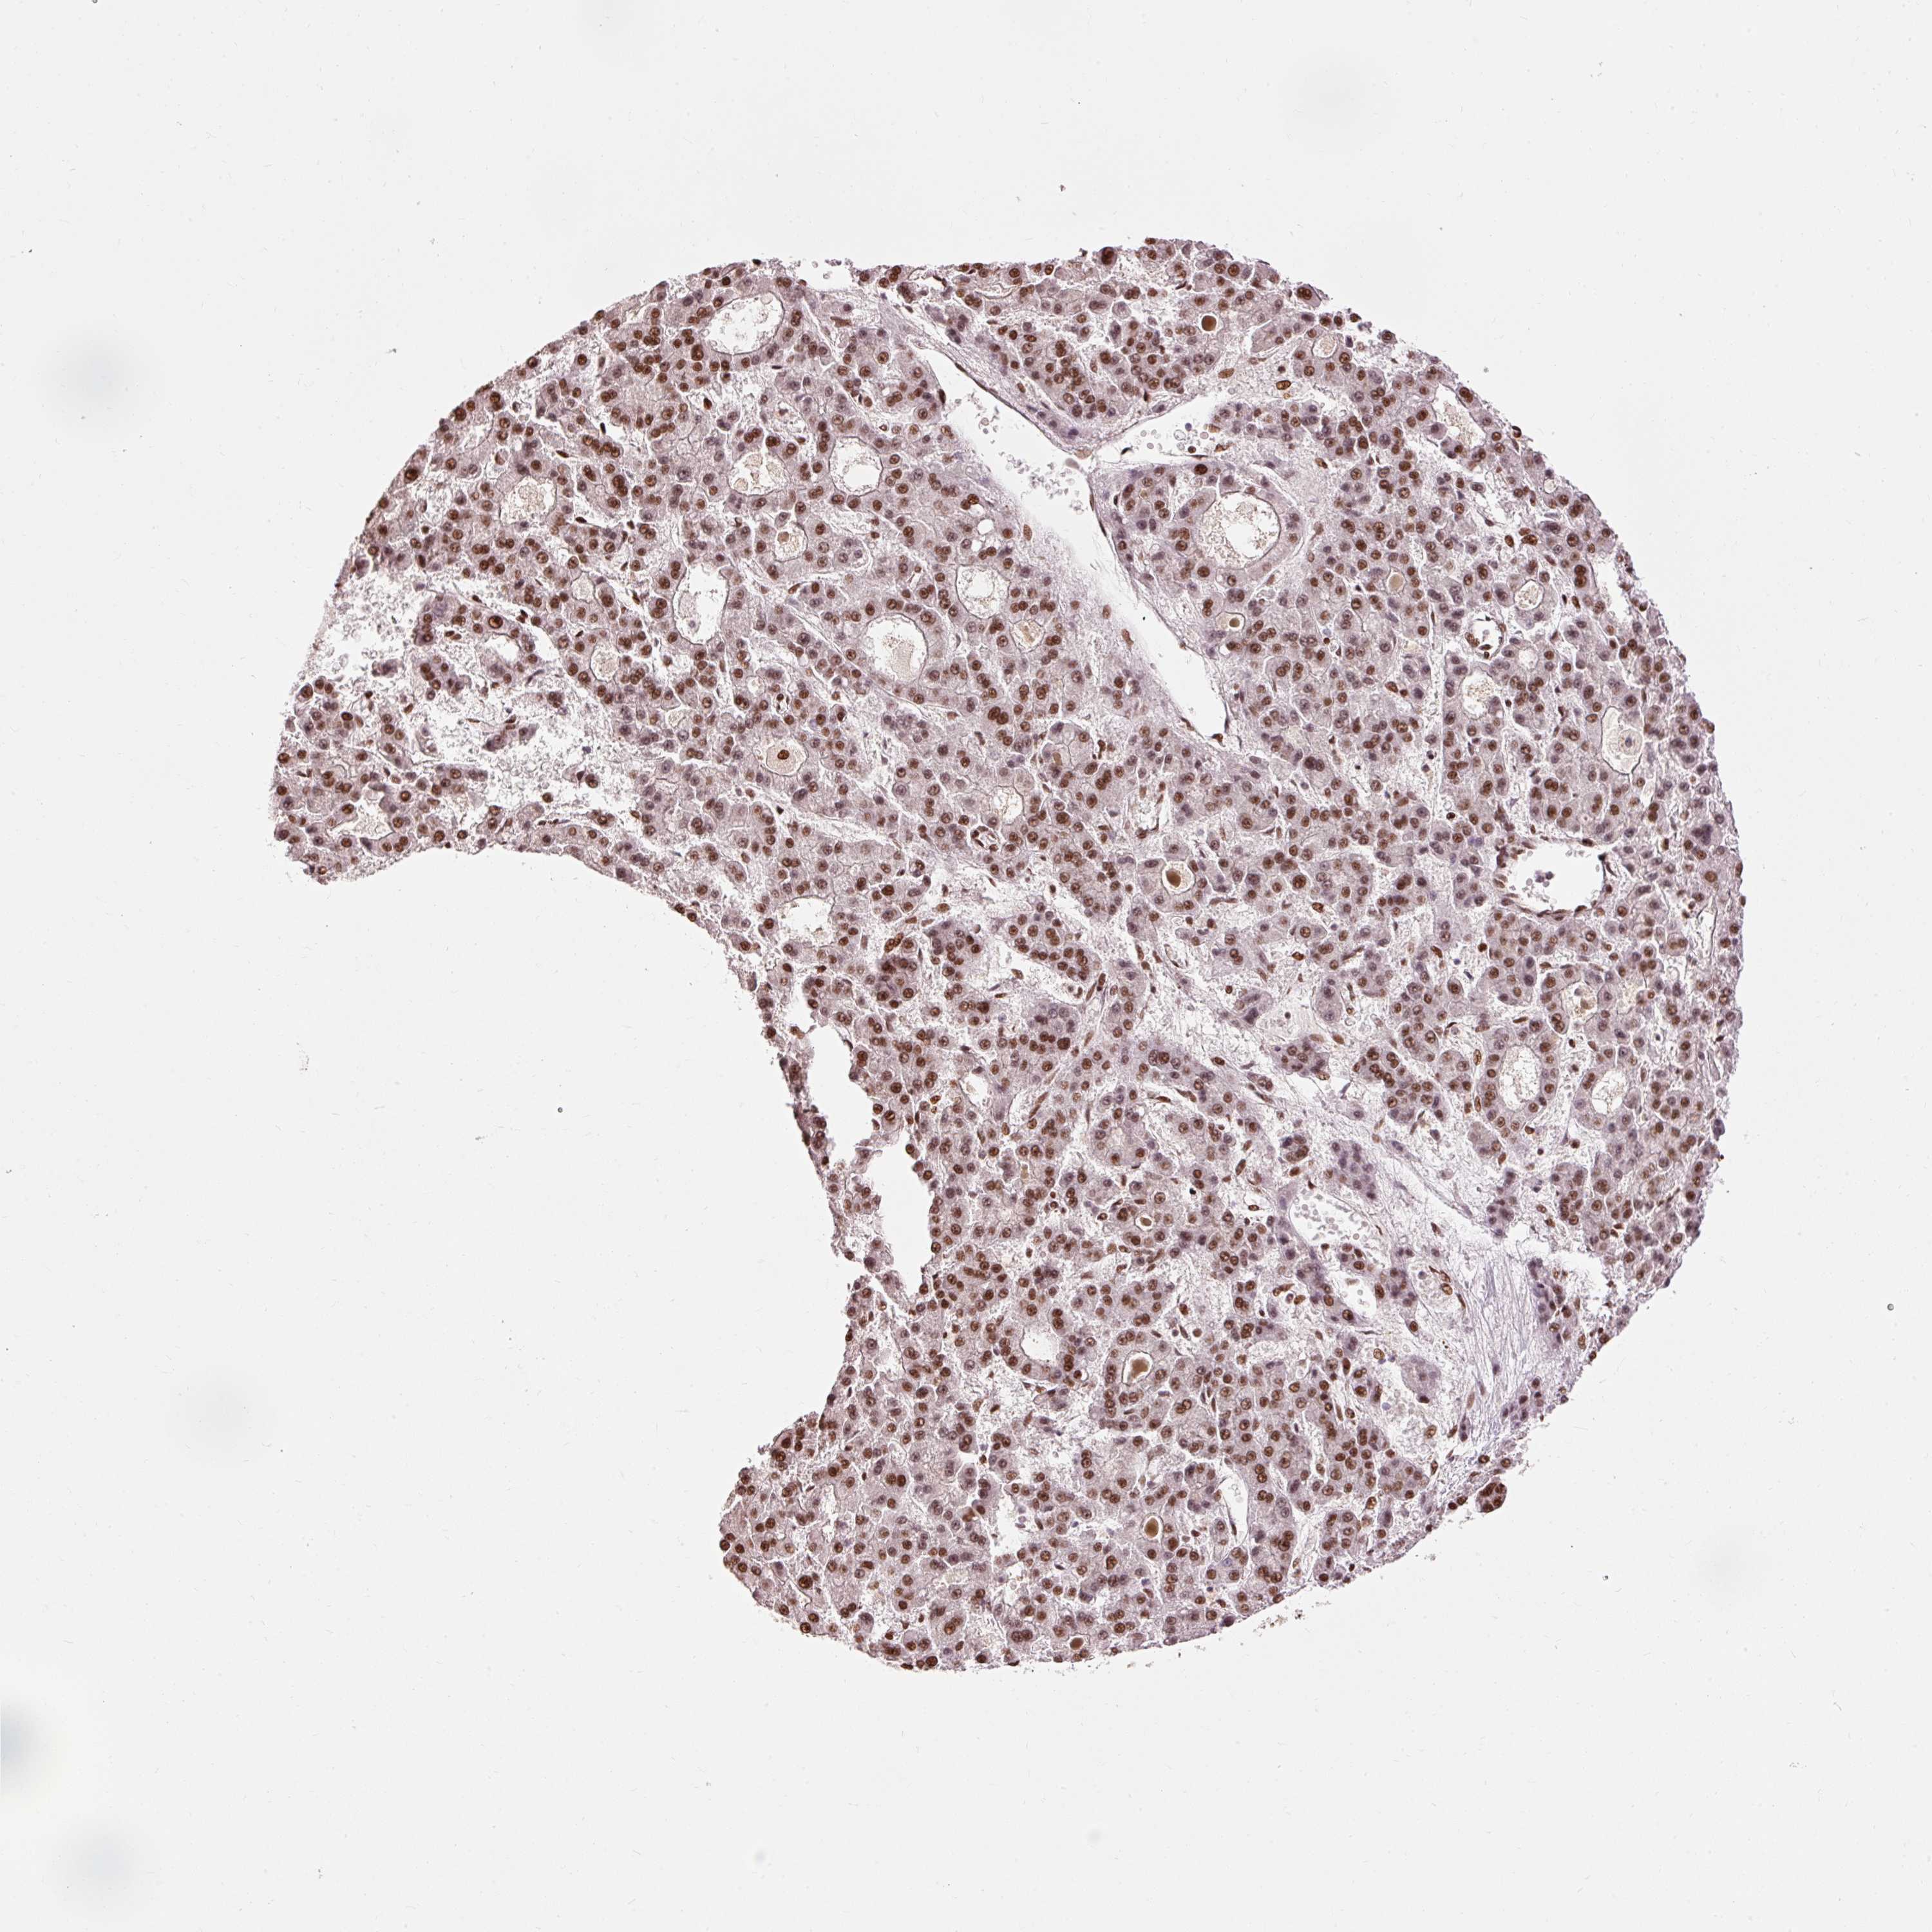

LIVER CANCER - Protein expressioni

A mouse-over function shows sample information and annotation data. Click on an image to view it in a full screen mode. Samples can be filtered based on level of antibody staining by selecting one or several of the following categories: high, medium, low and not detected. The assay and annotation is described here.

Note that samples used for immunohistochemistry by the Human Protein Atlas do not correspond to samples in the TCGA dataset.

Antibody stainingi

Antibody staining in the annotated cell types in the current human tissue is reported as not detected, low, medium, or high, based on conventional immunohistochemistry profiling in selected tissues. This score is based on the combination of the staining intensity and fraction of stained cells.

Each image is clickable and will lead to virtual microscopy that enables deeper exploration of all samples and also displays staining intensity scores, fraction scores and subcellular localization as well as patient and tissue information for each sample.

Antibody HPA052589

Staining

High

Medium

Low

Not detected

Intensity

Strong

Moderate

Weak

Negative

Quantity

>75%

75%-25%

<25%

None

Location

Nuclear

Cytoplasmic/membranous

Cytoplasmic/membranous,nuclear

Cholangiocarcinoma

Carcinoma, Hepatocellular, NOS